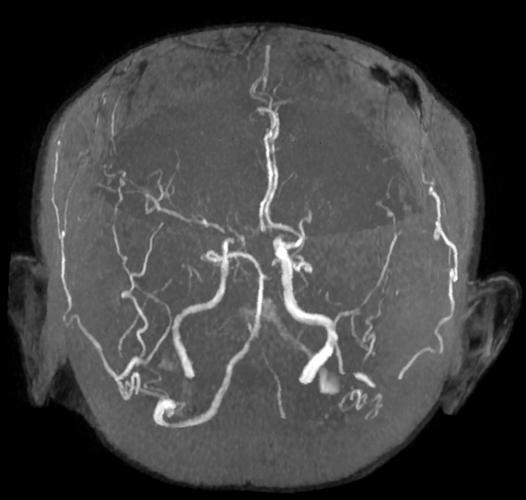

磁共振血管成像 是一种无创的检查技术,用于观察血管的结构和血流情况,而 脑梗 是因脑部血管堵塞导致脑组织缺血坏死的疾病。MRA是诊断、评估和指导脑梗治疗的关键工具。

MRA是磁共振成像的一个特殊应用,它不需要像传统血管造影那样向血管内注射造影剂(虽然也可以用),主要利用血液流动的特性来生成血管的图像。

- 时间飞跃法: 最常用的一种,利用血液流动速度快而周围组织静止的特点,流动的血液在图像上呈现为高信号(亮白色),而静止的组织呈低信号(黑色),从而形成血管的“造影像”。

MRA能显示什么?

- 血管有无狭窄或闭塞: 这是最核心的应用。